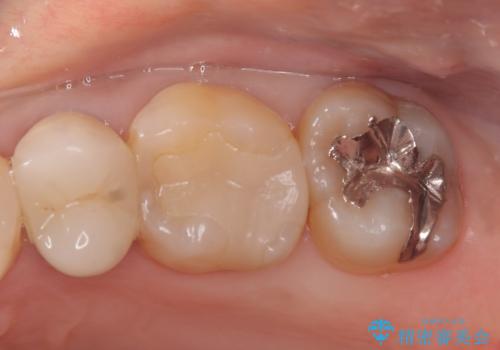

- 定期検診にて虫歯が見つかった患者様です。

金属のインレーの下と、歯と歯の間も虫歯だったため、つなげた形でセラミックインレーにて修復を行なっています。